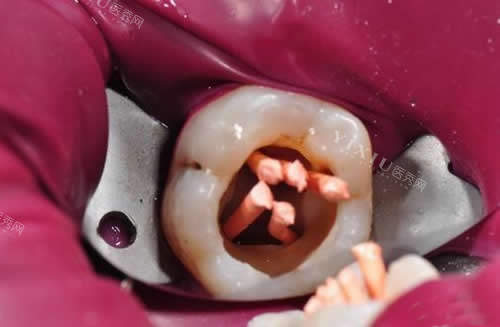

根管治疗图示

根管治疗手术过程

根管治疗过程示意图

根管治疗细节图片